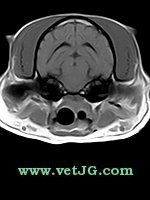

RESONANCIA MAGNÉTICA

AXIAL